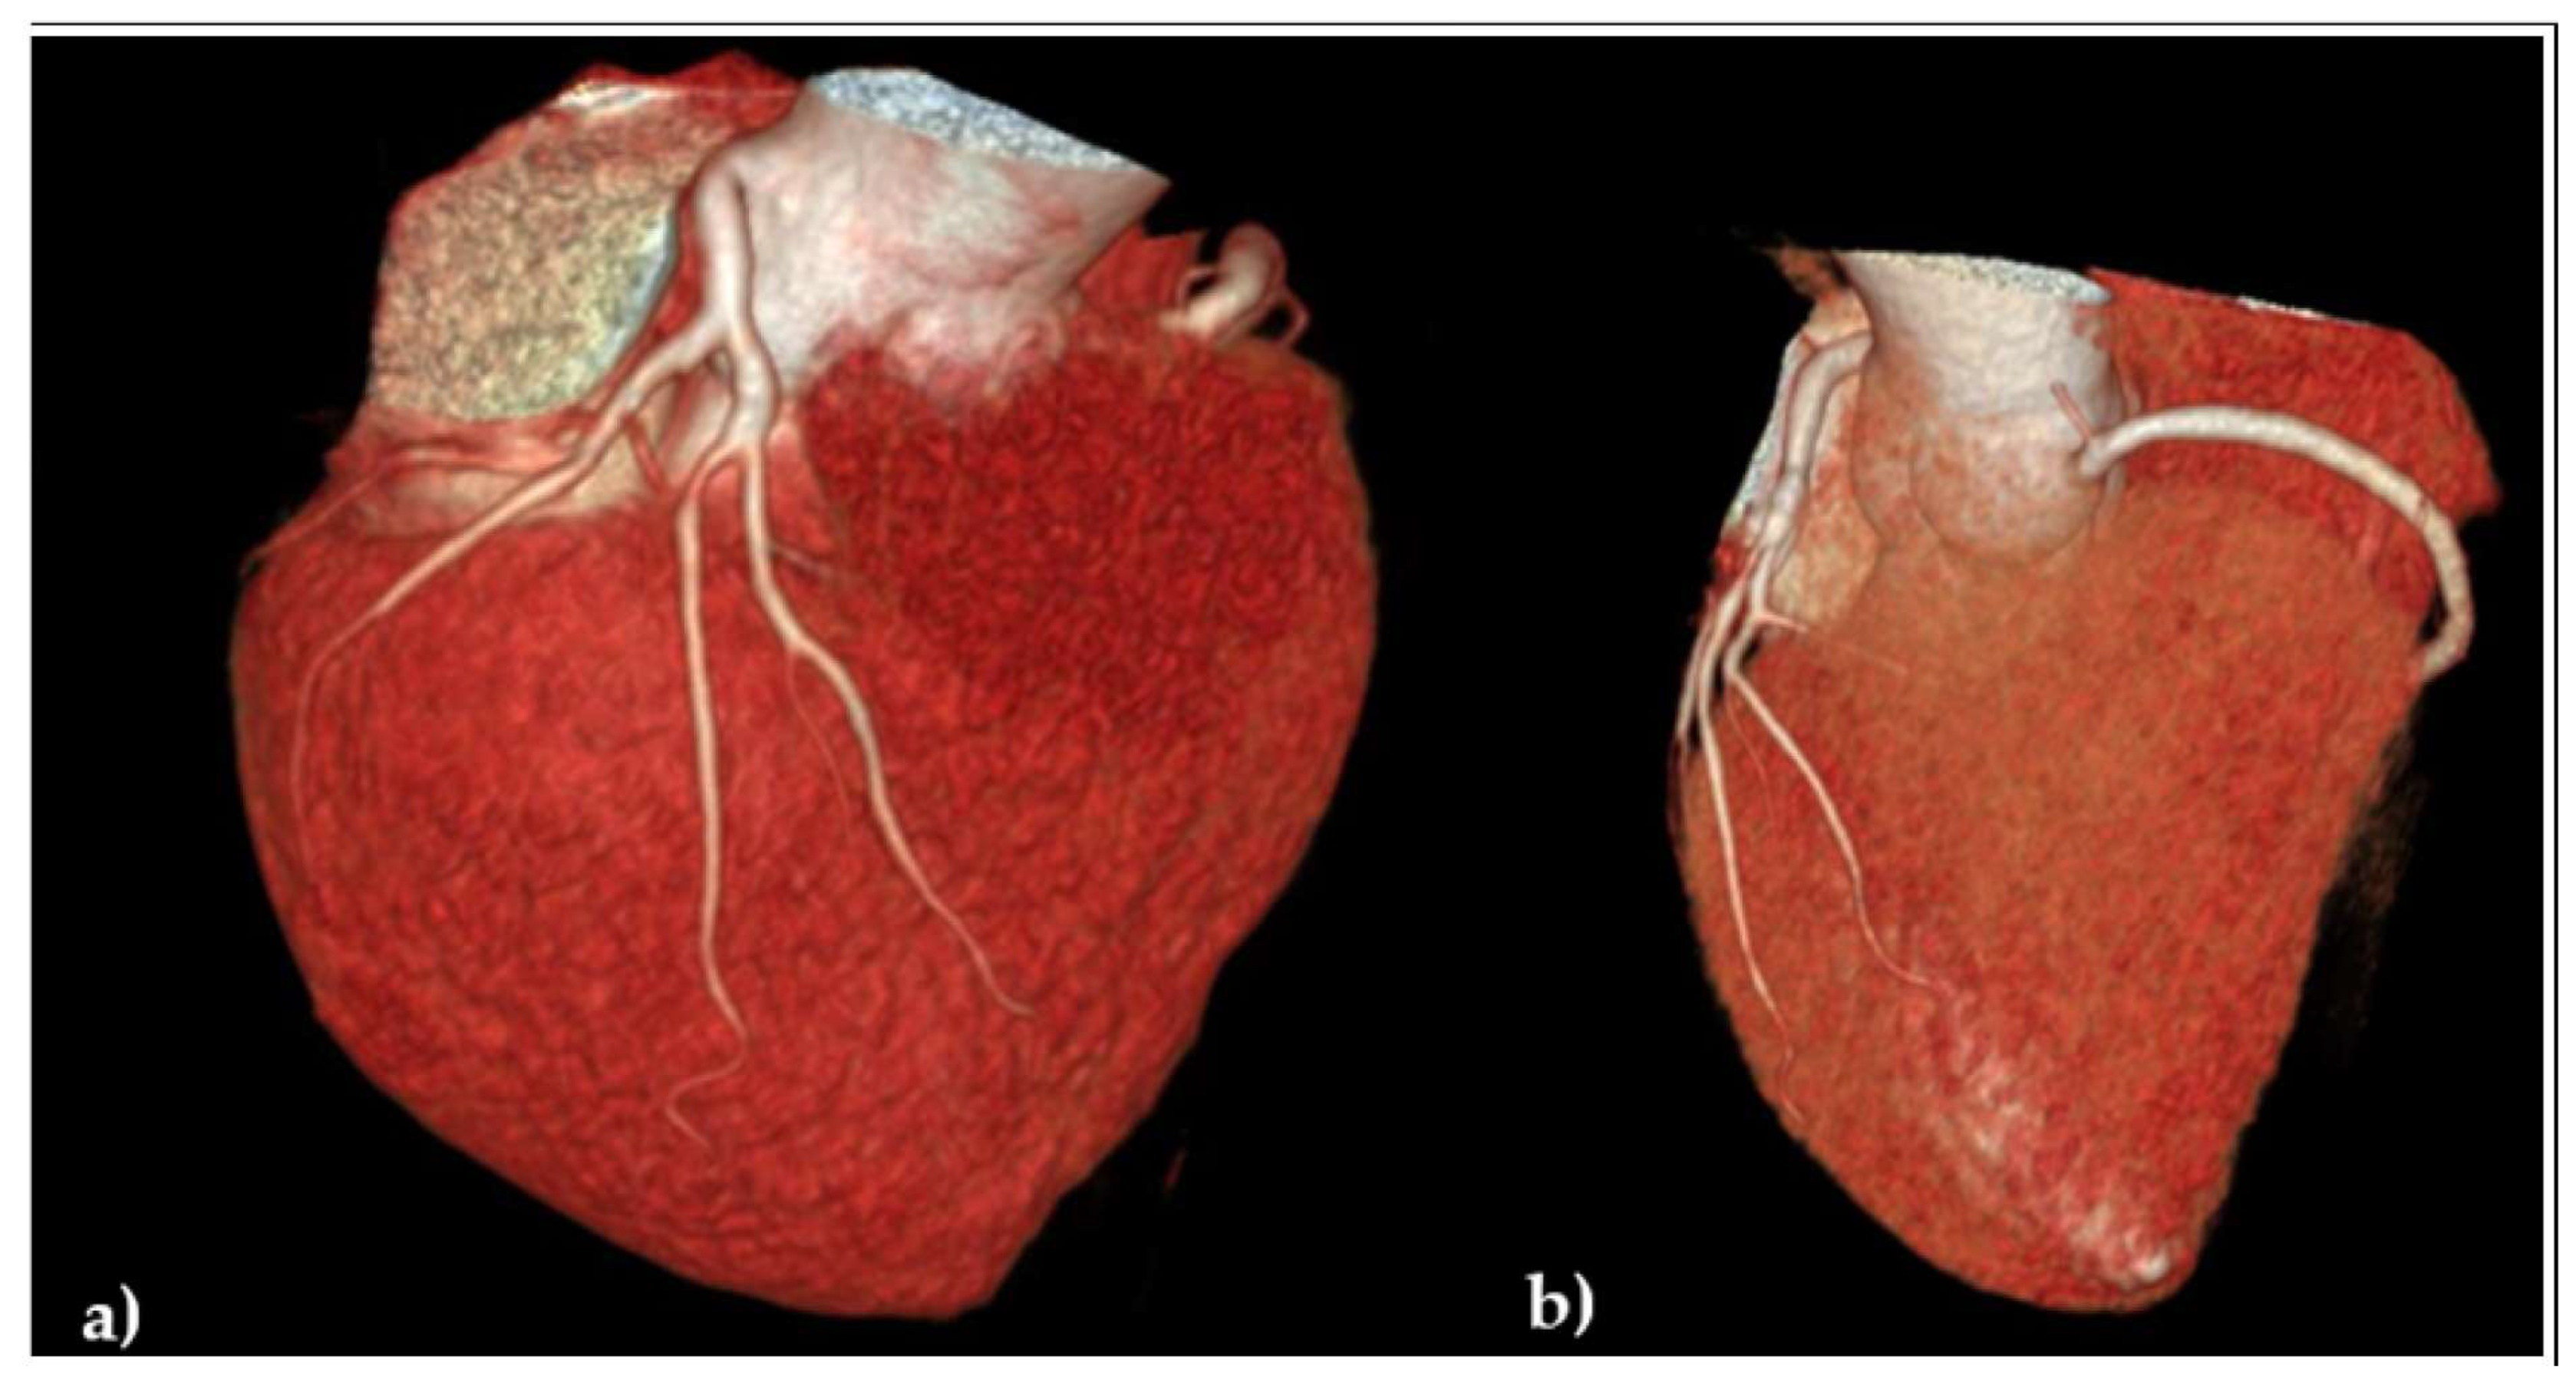

2.4. Diagnosis of Heart Failure, Initiation of Guideline-Guided Therapy, and Evolution